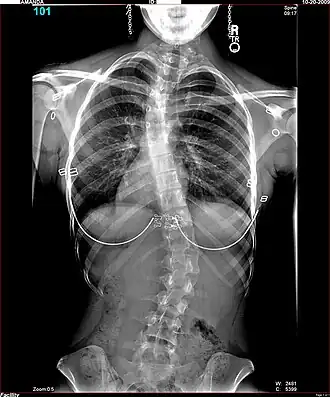

Radiografía de una joven de 16 años y 8 meses con escoliosis vista de frente, de pie y con ropa (los pendientes y los aros del sostén son claramente visibles) | ||

Es habitual que cuando se sospecha de escoliosis, se tomen radiografías del tórax en planos anteroposterior/coronal, y lateral/sagital, para evaluar las curvas de la escoliosis, además de las curvas normales de cifosis y lordosis, ya que estas también pueden estar afectadas en personas con escoliosis. Los rayos X de la columna en un paciente de pie, son el método estándar para evaluar la severidad y progresión de la escoliosis, y si es de naturaleza congénita o idiopática. En individuos en crecimiento, las radiografías seriales se obtienen en intervalos de 3-12 meses para seguir la progresión de la curvatura, y en algunos casos, se necesita además de resonancia magnética para examinar la médula espinal.

El método estándar para evaluar cuantitativamente la curvatura es la medida del ángulo de Cobb, el cual es el ángulo entre dos líneas, dibujado perpendicularmente a la placa terminal superior de la vértebra más superior involucrada y la placa terminal inferior de la vértebra más inferior afectada. Para los pacientes que tienen dos curvas, los ángulos de Cobb se siguen para ambas curvas. En algunos pacientes, se obtienen rayos X con inclinación lateral para evaluar la flexibilidad de las curvas o las curvas primaria y de compensación.